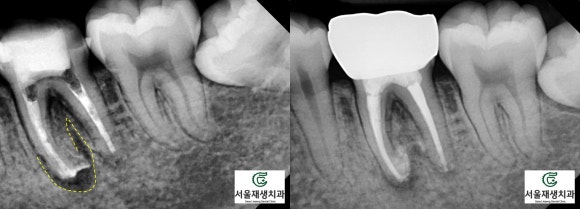

한 눈에 보기에도 병소의 크기가 꽤나 크지요?

치아가 뿌리 끝에 자기 몸뚱이만큼이나 큰 물혹을 달고 있습니다.

<병소가 큰 재신경치료 케이스의 비포 애프터>

(9개월 소요)

(8개월 소요)

(6개월 소요)